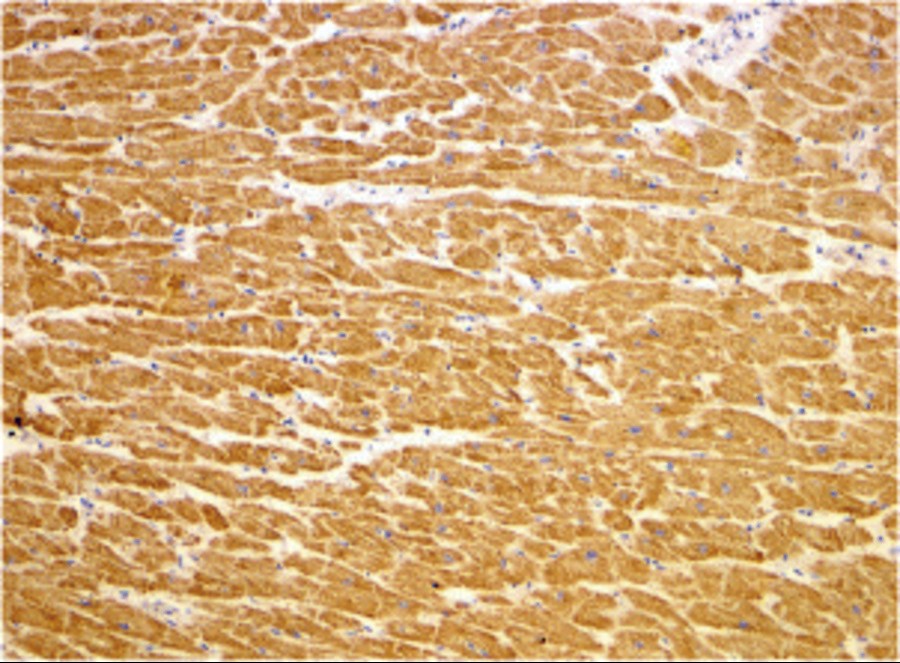

Product information "Anti-TIRAP"

Protein function: Adapter involved in the TLR2 and TLR4 signaling pathways in the innate immune response. Acts via IRAK2 and TRAF-6, leading to the activation of NF-kappa-B, MAPK1, MAPK3 and JNK, and resulting in cytokine secretion and the inflammatory response. Positively regulates the production of TNF-alpha and interleukin-6. [The UniProt Consortium]

| Application: | IHC (paraffin), WB |

| Immunogen: | Synthetic peptide around 15 aa (C-terminus) of Mouse TIRAP |